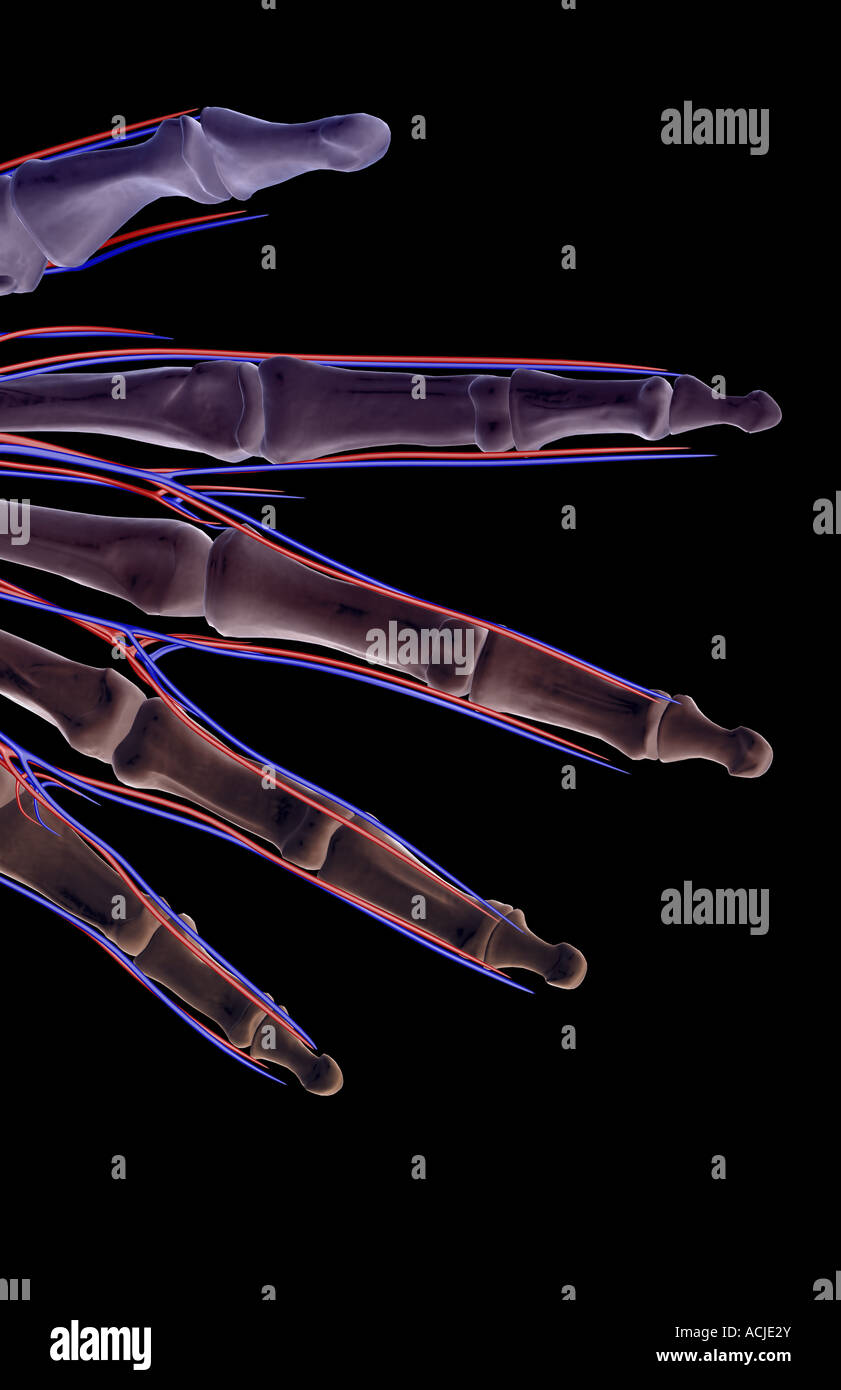

The blood supply of the fingers Stock Photohttps://www.alamy.com/image-license-details/?v=1https://www.alamy.com/stock-photo-the-blood-supply-of-the-fingers-13169666.html

The blood supply of the fingers Stock Photohttps://www.alamy.com/image-license-details/?v=1https://www.alamy.com/stock-photo-the-blood-supply-of-the-fingers-13169666.htmlRFACJE2Y–The blood supply of the fingers